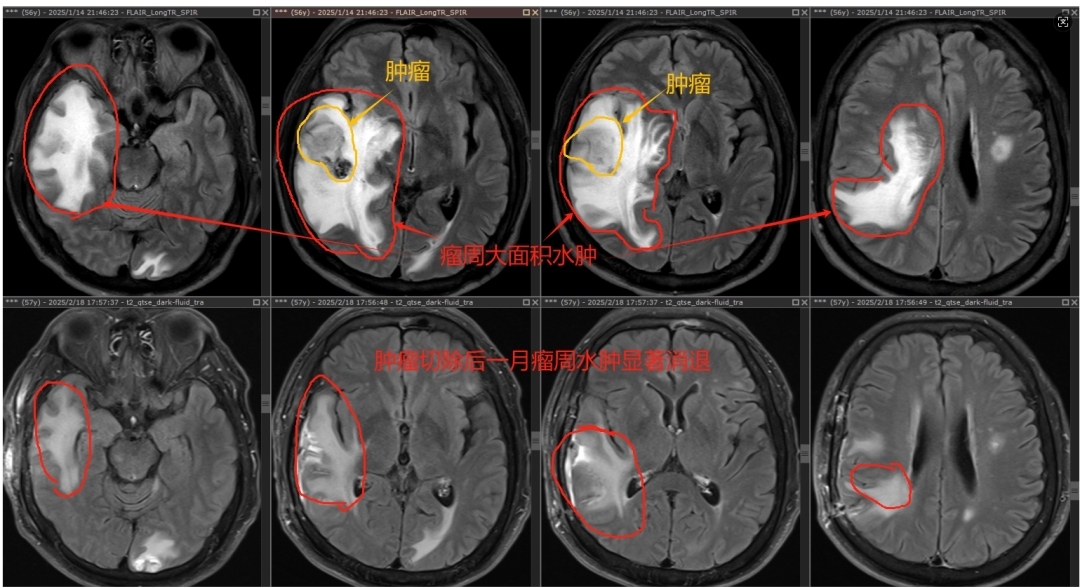

56岁的坚叔(化名)查出肺癌时已伴有颅内多发转移,不适合肺癌切除手术,其中右颞叶转移瘤最大径足有3.75厘米,肿瘤周围大面积脑水肿,硬生生地将大脑中线结构挤到移了位,颅内压力明显增高,出现无法缓解的头晕、头痛等症状。

“在这种情况下,如果贸然放疗,对肿瘤的‘攻击’不一定会有效,而脑水肿必然会加重,很有可能闯不过放疗后脑水肿加重的难关,如果发生脑疝,那就更危险了。”广州医科大学附属第一医院神经外科学科主任、主任医师夏成雨仔细为坚叔评估病情后,决定先为他施行手术切除右颞叶转移瘤。术后,坚叔的颅内高压“警报”症状“头痛头晕恶心”逐渐解除,术后一月复查原本被肿瘤和大面积脑水肿推挤移位的脑中线结构逐渐归位了,肿瘤周围的脑水肿也显著消退了。

坚叔治疗前后检查结果对比。